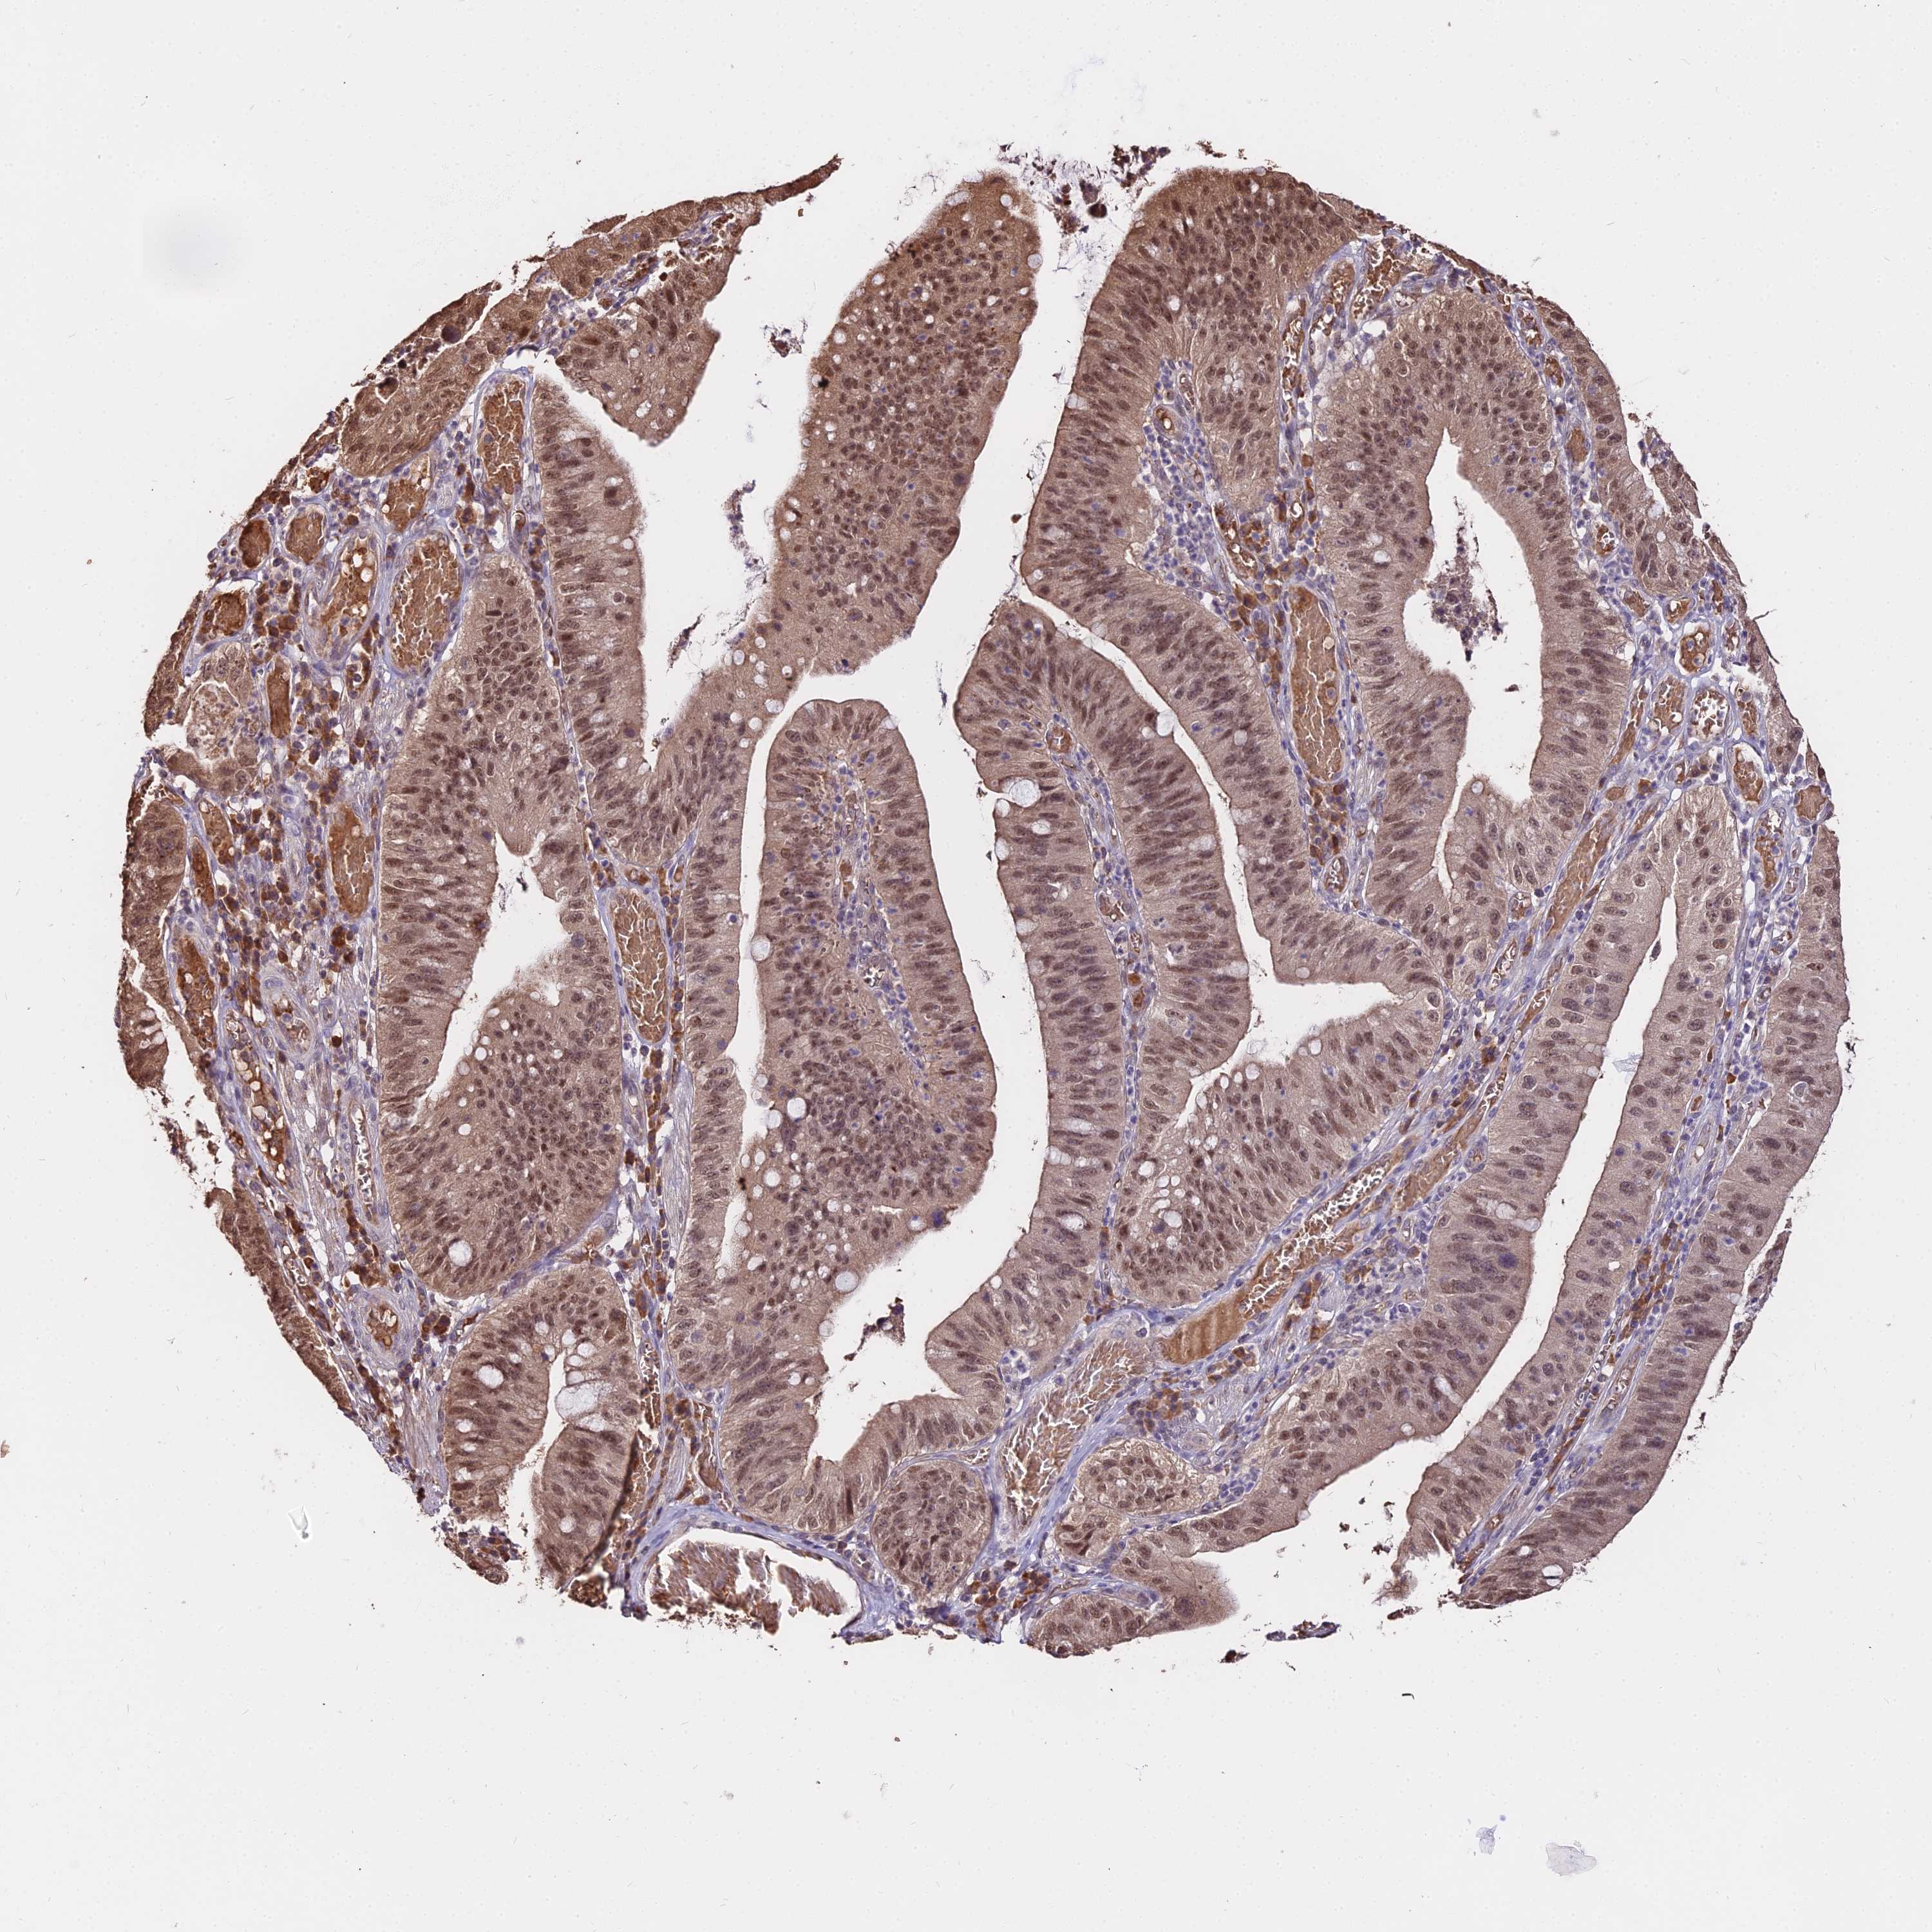

STOMACH CANCER - Protein expressioni

A mouse-over function shows sample information and annotation data. Click on an image to view it in a full screen mode. Samples can be filtered based on level of antibody staining by selecting one or several of the following categories: high, medium, low and not detected. The assay and annotation is described here.

Note that samples used for immunohistochemistry by the Human Protein Atlas do not correspond to samples in the TCGA dataset.

Antibody stainingi

Antibody staining in the annotated cell types in the current human tissue is reported as not detected, low, medium, or high, based on conventional immunohistochemistry profiling in selected tissues. This score is based on the combination of the staining intensity and fraction of stained cells.

Each image is clickable and will lead to virtual microscopy that enables deeper exploration of all samples and also displays staining intensity scores, fraction scores and subcellular localization as well as patient and tissue information for each sample.

Antibody HPA039121

Staining

High

Medium

Low

Not detected

Intensity

Strong

Moderate

Weak

Negative

Quantity

>75%

75%-25%

<25%

None

Location

Nuclear

Cytoplasmic/membranous

Cytoplasmic/membranous,nuclear

Adenocarcinoma, NOS